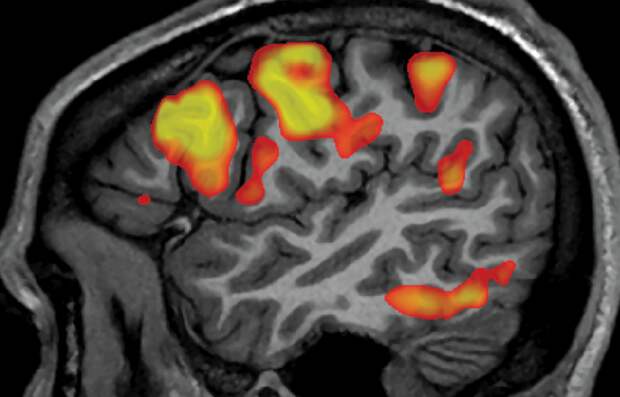

Сотрудники Техасского университета в Остине разработали интерфейс на основе функциональной магнитно-резонансной томографии (фМРТ). Она позволяет следить за активностью определенных областей головного мозга во время его функционирования, причем обладает высоким разрешением. Иногда данную технологию применяют для отслеживания кровотока в мозге. Ранее мы рассказывали, что при помощи фМРТ, в ходе одного из исследования ученые отслеживали уровень стресса у людей.

В данном же случае фМРТ следит за той частью мозга, которая отвечает за воображаемую речь человека. На каждое слово мозг человека реагирует особым образом. Поэтому задача ученых состояла в том, чтобы связать каждое слово с определенным паттерном мозговой активности. Для этого команда сканировала мозг трех людей в течение 16 часов, пока они слушали подкасты.

Искусственный интеллект распознает слова и фразы по активности мозга

Таким образом команда смогла создать определенный набор карт активностей мозга, вызванных разными словами, фразами или значениями фраз. Затем авторы обучили искусственный интеллект определять о чем думает человек на основе данных фМРТ. В отличие от разработок, которые существовали ранее, данная технология не распознает отдельные слова, а определяет общее значение каждой фразы или предложения.